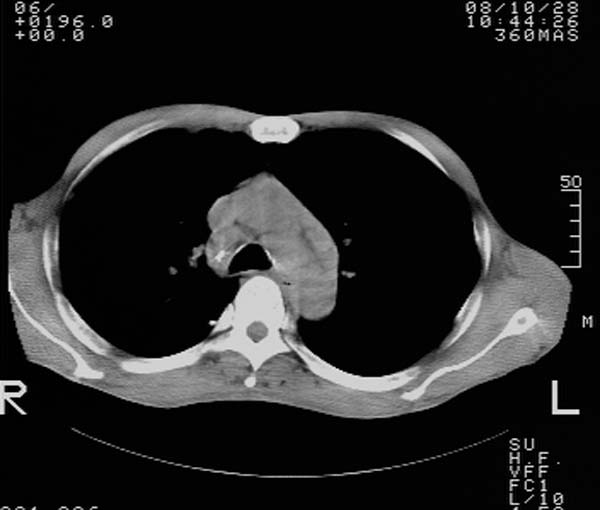

m,65y。半年前发现颈小结节,逐渐增多增大,现双侧耳后、颌下及颈部表浅淋巴肿大。胸片示双肺门增大。外院曾穿刺诊断为淋巴结核。在我科作胸腹部ct,我们觉得外院病检有误。现将图像上传请战友讨论。

纵隔内及腹膜后广泛淋巴结肿大,脾大,肝内似可见低密度影,结合病史半年前发现颈小结节,逐渐增多增大,现双侧耳后、颌下及颈部表浅淋巴肿大。考虑淋巴瘤。

纵隔,双肺门腹膜后多发淋巴结重大,非融合,肝脾轻度肿大,双肺野弥漫性小结节;考虑淋巴瘤,结节病可能性

纵隔内,双肺门、腋窝及腹膜后多发肿大淋巴结影,肺内小结节影,肝脾体积增大,支持淋巴瘤。肝内多发低密度影,考虑小囊肿。

考虑淋巴瘤肺、肝内转移,脾脏肿大。

纵隔内,双肺门、腹膜后多发肿大淋巴结影及颈部淋巴结肿大,肝脾体积大.结合临床,淋巴瘤可能性大。